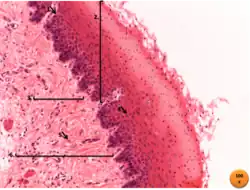

- Capa mucosa: Conformada por el epitelio y el tejido conectivo subyacente. El epitelio#Epitelio estratificado plano no queratinizado tiene varias capas de células y recubre la luz del esófago. Este epitelio está renovándose continuamente por la formación de nuevas células de sus capas basales. Para facilitar la propulsión del alimento hacia el estómago, el epitelio está recubierto por una fina capa de mucus, la cual se forma por las glándulas cardiales y esofágicas. El tejido conectivo es de tipo laxo, y se separa de la siguiente capa (submucosa) por medio de la capa muscularis mucosae.

- Capa submucosa: capa que se encuentra por debajo de la mucosa, y está formada por tejido conectivo denso, se encuentran en ella glándulas esofágicas.

- Capa muscular: está formada por dos capas de músculo liso, una capa interna de células de dirección circular y otra capa externa de células musculares longitudinales, que cuando se contraen forman ondas peristálticas que conducen el bolo alimenticio al estómago.

- La capa muscular es más flexible y las mediciones biomecánicas han demostrado que tiene un módulo de elasticidad menor. Esta diferencia de rigidez/flexibilidad implica que la distribución de esfuerzos en un esófago no puede ser uniforme.

- Capa serosa o adventicia: Formada por tejido conectivo, excepto en la región del receso vertebromediastinico, donde las pleuras lo revisten parcialmente.[4]

Capas del esófago. -